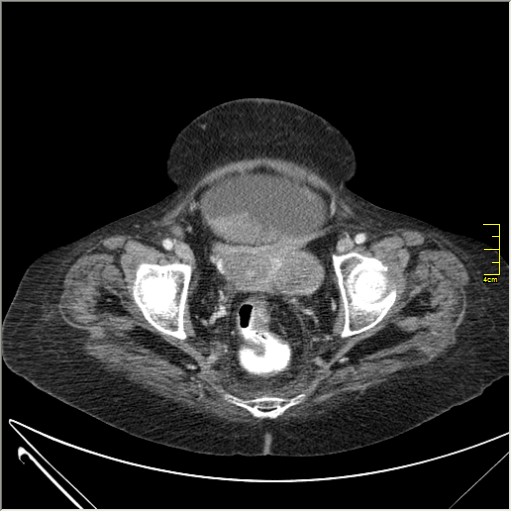

Женщина 72 года. Поступила с жалобами на вздутие живота. После осмотра хирургом, была сразу направлена на КТ брюшной полости.

Итак, асцит с объёмным образованием таза. В данном случае можно быть более конкретным, у пациентки неоплазия правого яичника с региональной лимфаденопатией (увидели?) и выраженным асцитом, характерным именно для злокачественных опухолей яичников. Пациентка оперирована ( операция Вертгейма); диагноз верифицирован: аденокарцинома правого яичника (серозная). Направлена к онкологу для дальнейшего лечения.